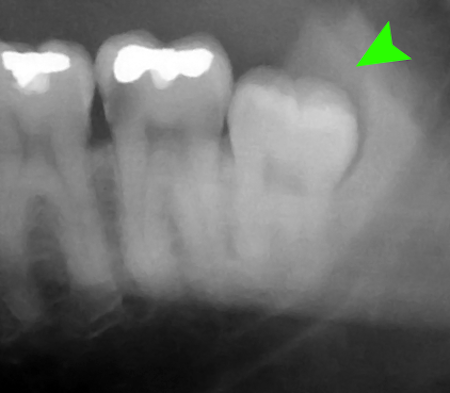

親知らずは奥まった位置に生えるため、まっすぐに生えてこない場合が多く、トラブルの原因となります。抜歯を検討すべき代表的なケースは以下の通りです。

- 斜めや横向きに生えている場合

隣の歯を押して痛みや歯並びの乱れを引き起こすことがあります。 - 歯ぐきの腫れや痛みを繰り返す場合

手前の歯との間に汚れが溜まりやすく、むし歯や歯周病を引き起こすことがあります。 - 嚢胞(のうほう)ができている場合